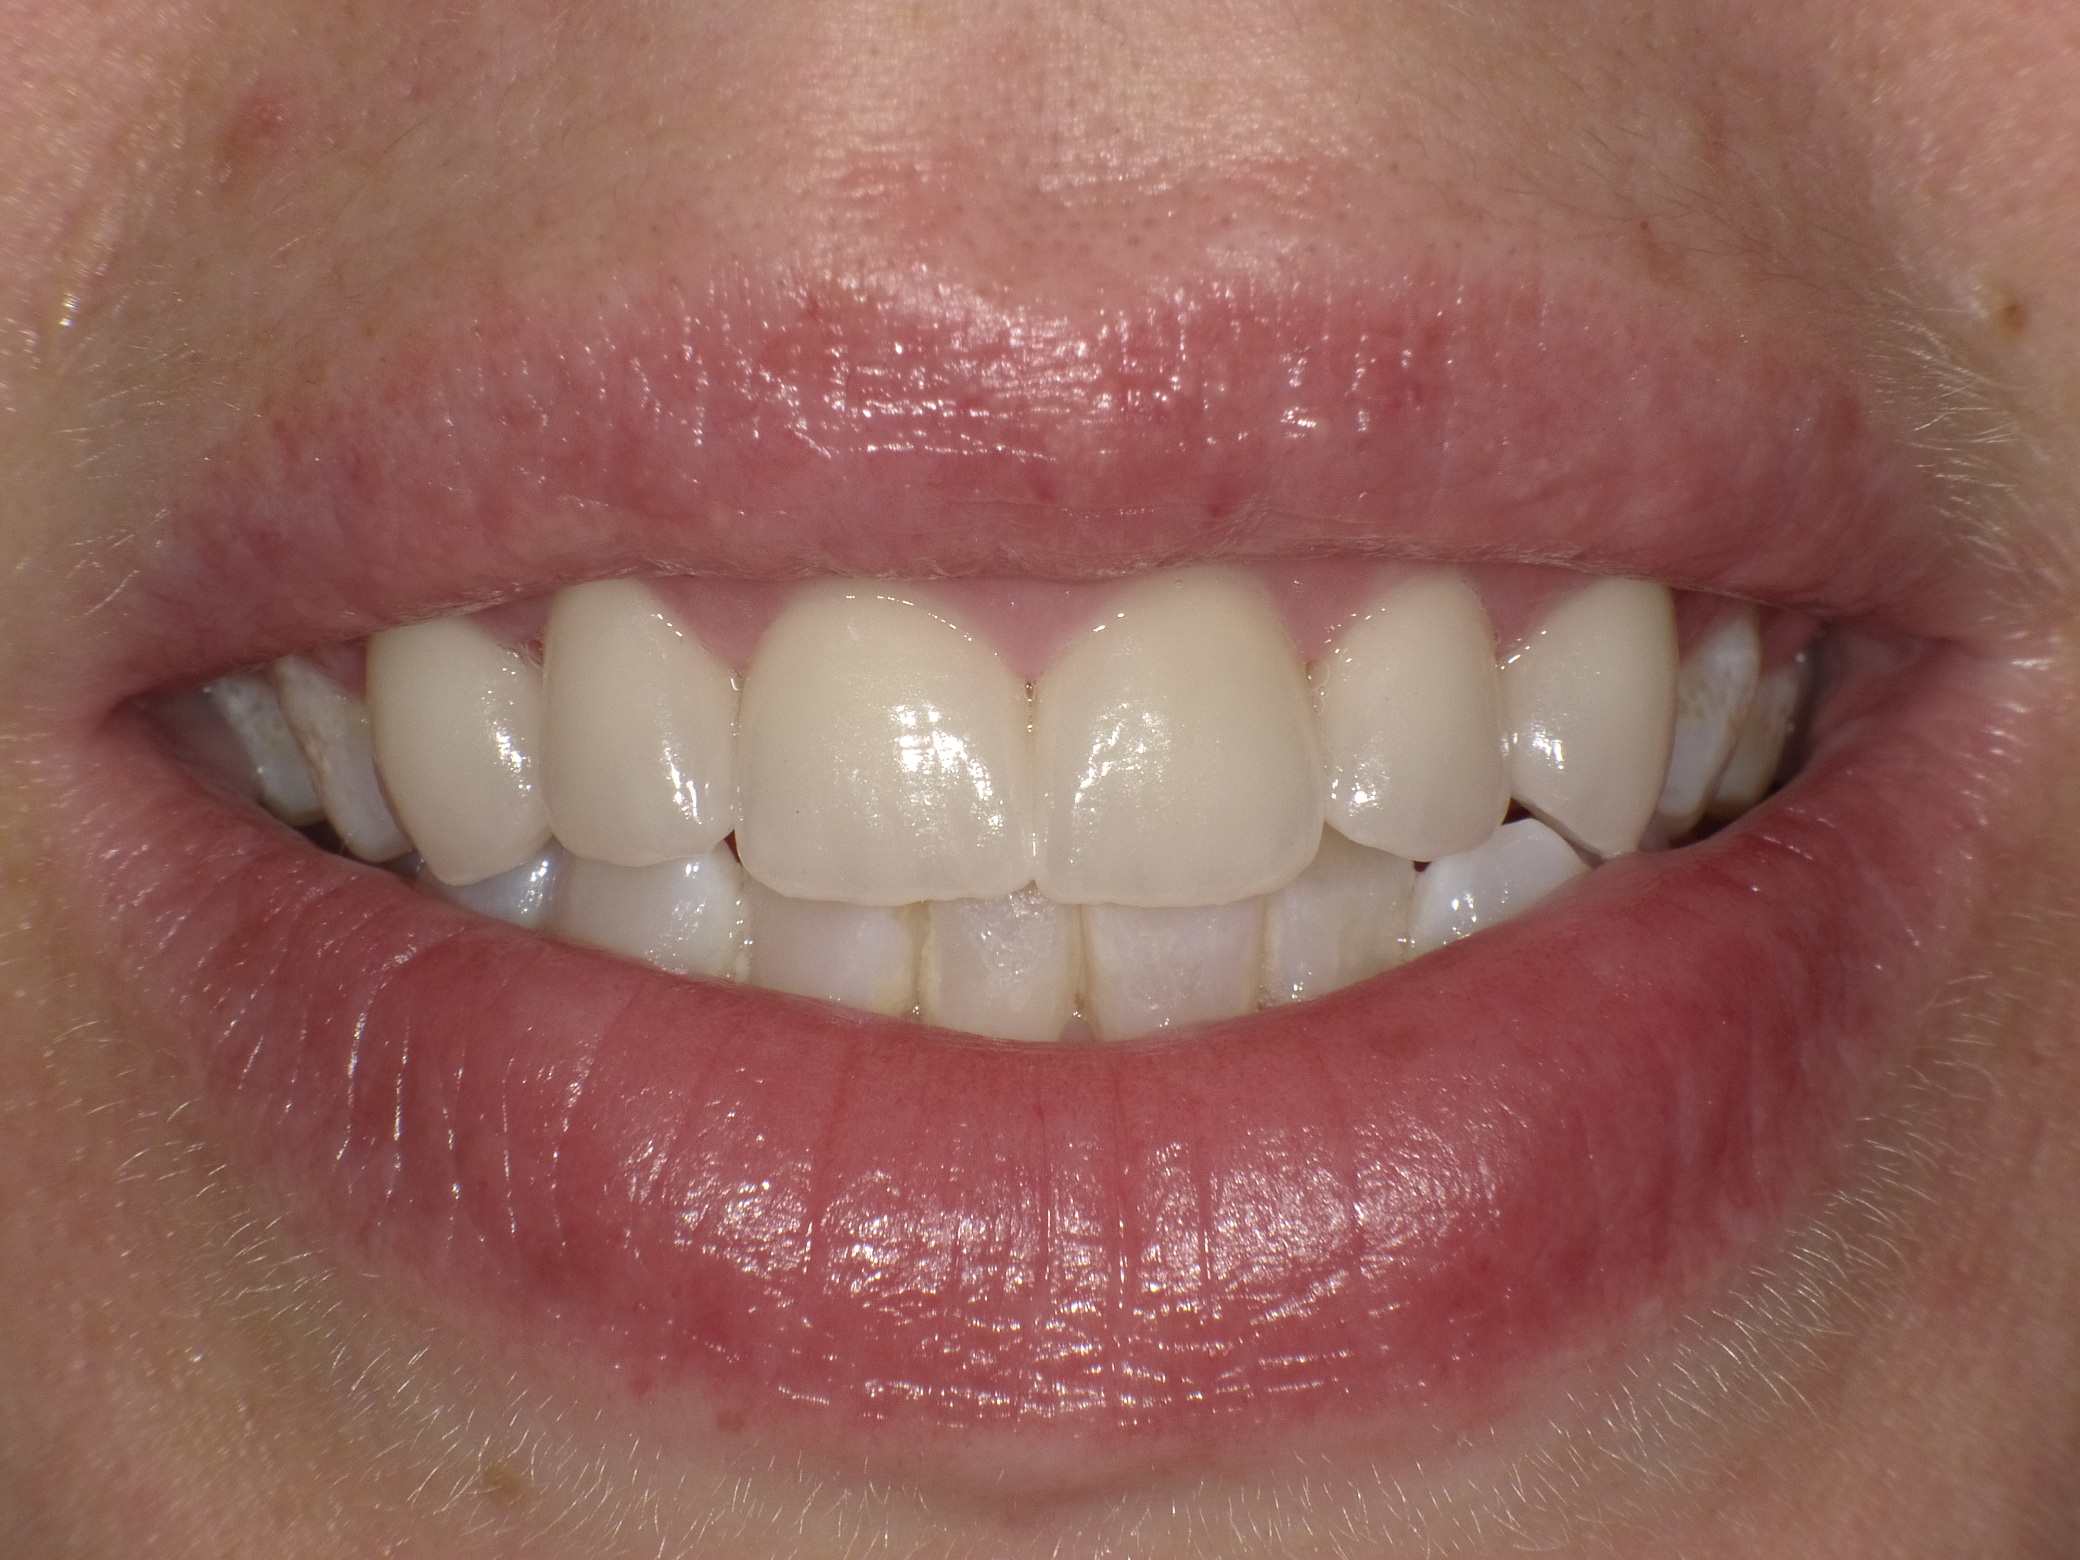

Diverse Vorbehandlungen mit für die Patientin absolut inakzeptablem Ergebnis

Vorher: Diverse Vorbehandlungen mit für die Patientin absolut inakzeptablem Ergebnis

Komplette Veränderung mit vollkeramischen Kronen und Veneers in nur 2 Langzeitterminen; auch hier nachher ganz anderes Auftreten der Patientin, die ihre Zähne jetzt gerne zeigt und wieder gerne lacht

Nachher: Komplette Veränderung mit vollkeramischen Kronen und Veneers in nur 2 Langzeitterminen; auch hier nachher ganz anderes Auftreten der Patientin, die ihre Zähne jetzt gerne zeigt und wieder gerne lacht